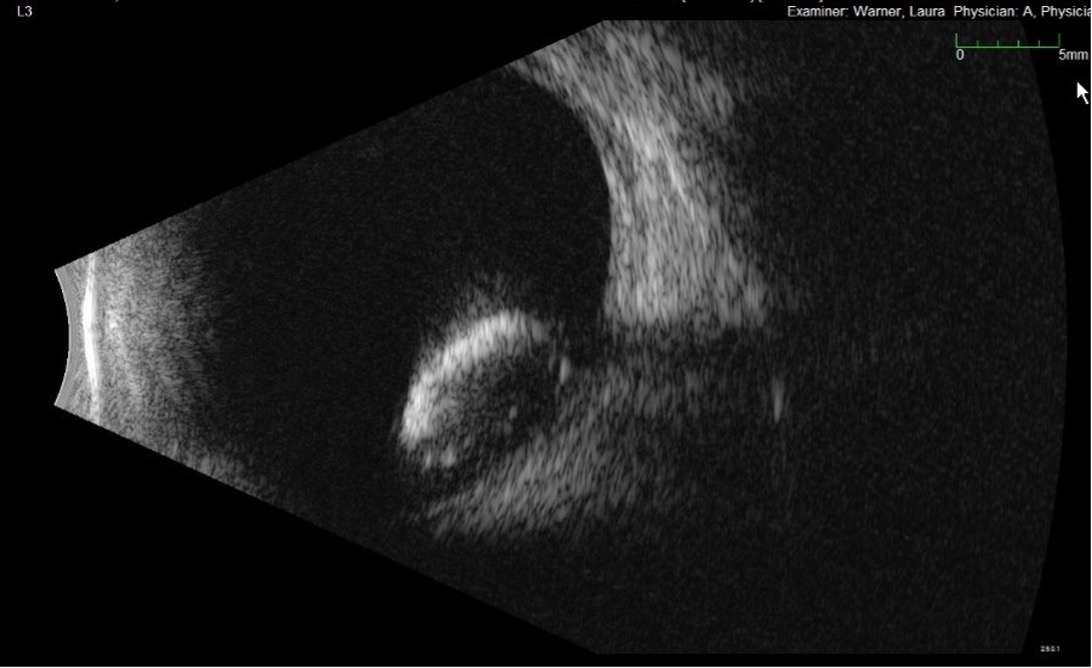

• B-scan ocular ultrasound was obtained in the left eye on initial presentation; findings are presented in Figures 2a, 2b (photos) and Figure 3 (video).

Figure 2a,2b. This is a formal B-scan oriented at L3 (2a, top) and T6E (2b, bottom), which shows the dense cataractous dislocated lens has fallen to the back and is resting on the retina. Notice the completely intact lens capsule.